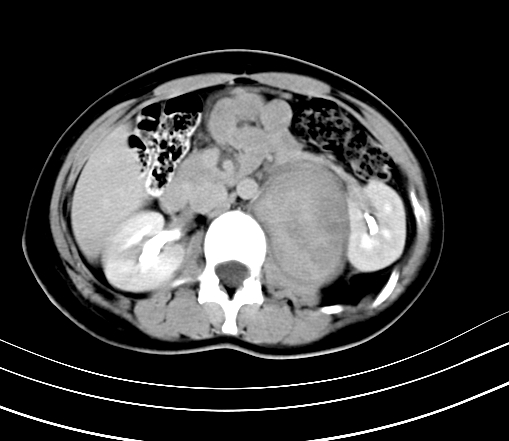

静脉期